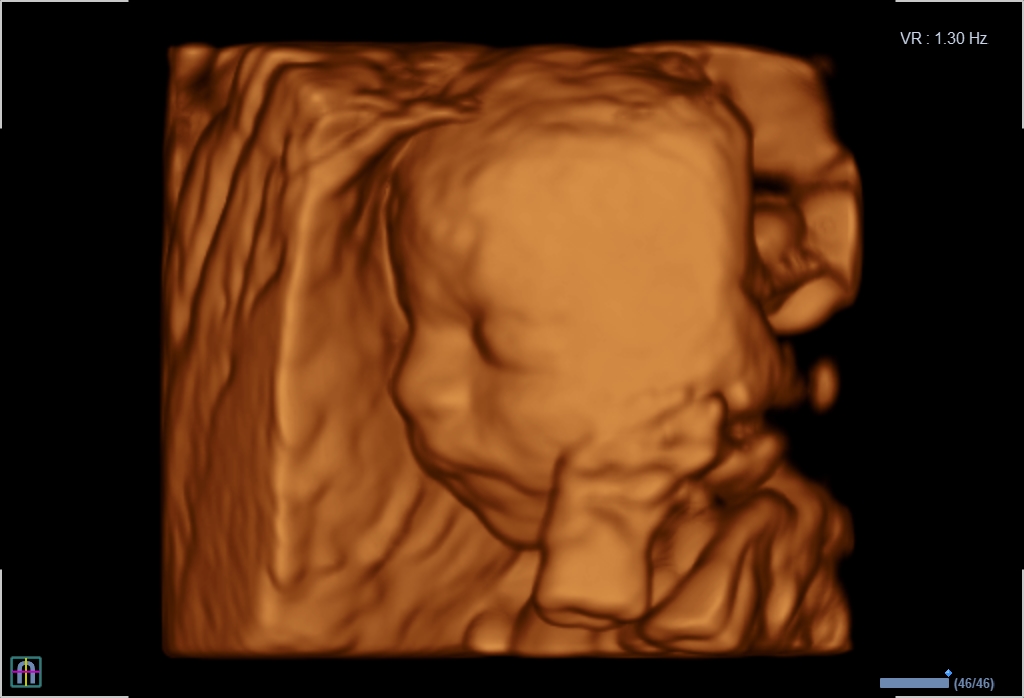

Seit März 2019 steht ein neues 3D/4D-Ultraschallgerät für faszinierende Eindrücke von Ihrem Baby zur Verfügung.

Außer den Fotos können auch 3D/4D Viedeoclips gemacht und auf einem USB-Stick gespeichert werden. So können die Bilder und Clips jederzeit angesehen werden.